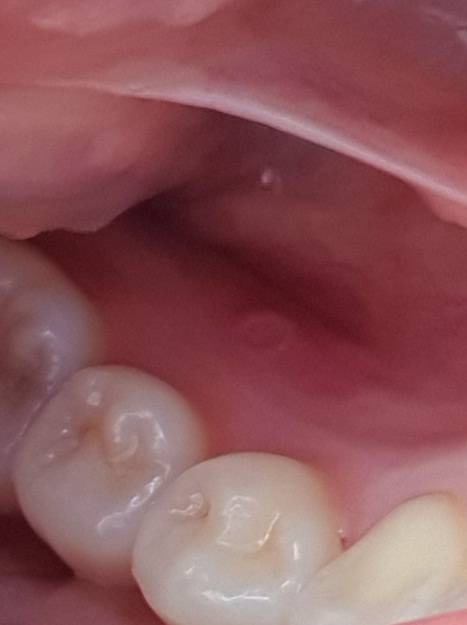

잇몸에 이상한거 생겼는데 이거 뭐지???(ㅇㅎ)

약간 홈? 같은거 생겼는데 저거 뭘까??? 너무 아픈데..

익인1

구내염?

익인2

아파?

구내염 같은데